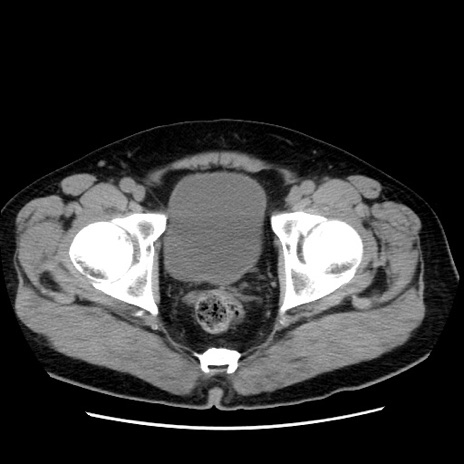

冠状断像